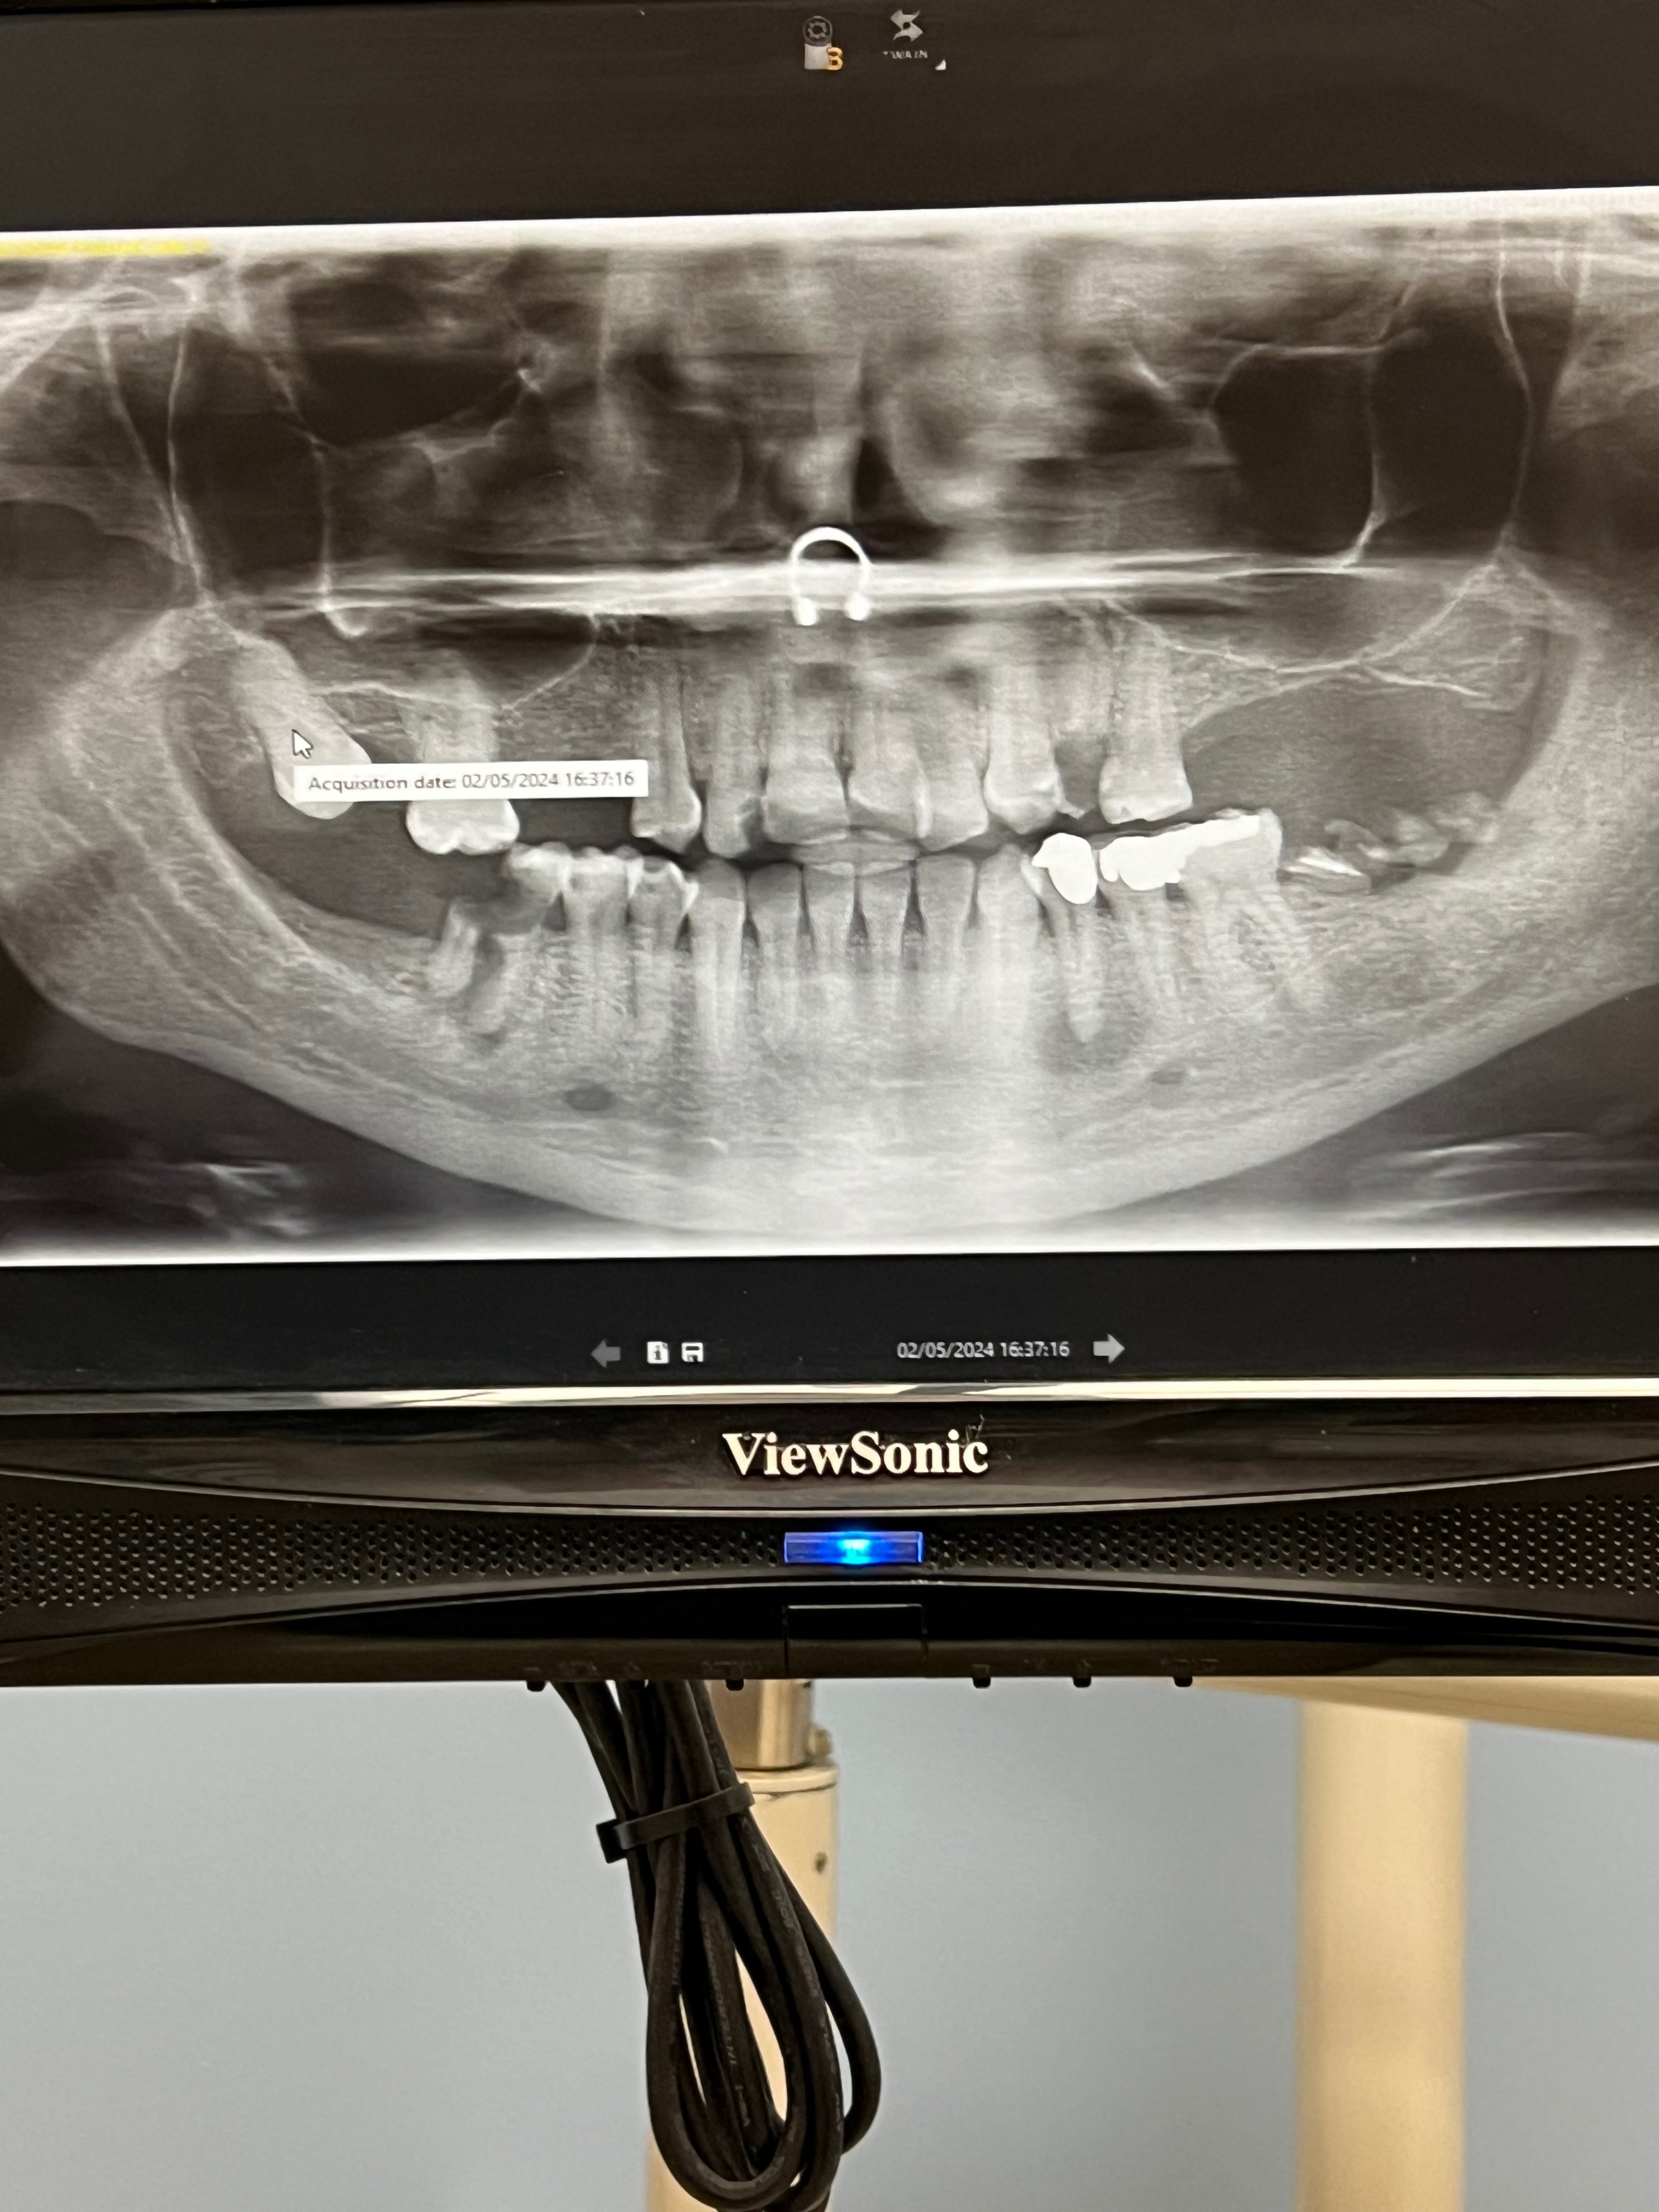

Hello there! My name is Bobiana, and I’m reaching out for your help. I’ve been struggling with a lot of dental issues that willcost me over $20,000 if I follow the recommended treatments. Unfortunately, my income is quite low, and I can’t afford the treatments or the ongoing care. I’m considering dentures as a more affordable option.

I’m thinking of having all my teeth removed and getting dentures. This would be the most cost-effective solution for me. It would cost around $10,000. Having bad teeth has had a terrible impact on my life. I’m ashamed to eat, talk, or smile in front of people. I’m constantly in pain and get frequent infections.